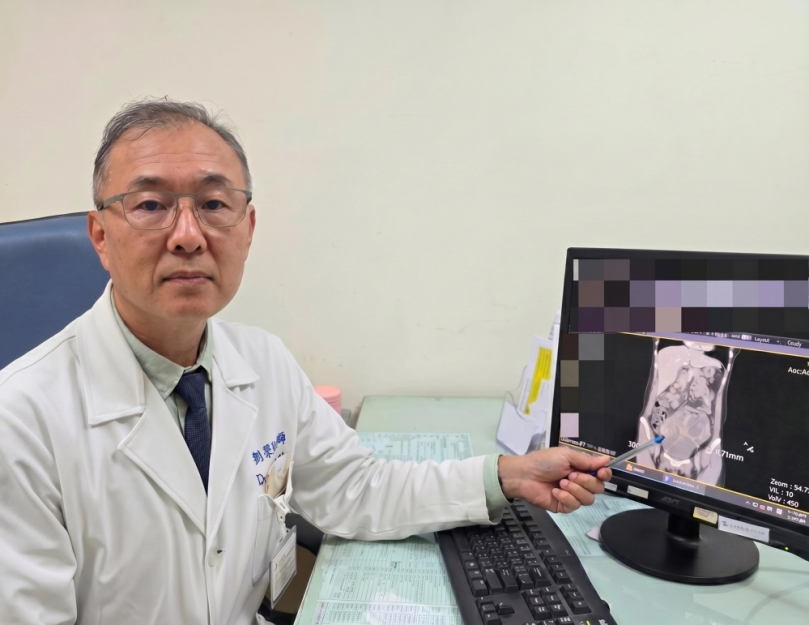

腹脹食慾差竟藏16公分巨瘤! 44歲女確診「同步雙癌」

(特派員劉鳳瑩、陳明/苗栗報導)一名44歲未婚女性,持續兩週感到腹痛、腹脹且食慾不振,原以為是腸胃不適,就醫檢查後竟在腹部發現直徑高達 16公分的巨大腫瘤,且癌症指數(CA-125)飆升至 900 U/ml(正常值為 <35 U/ml)。大千綜合醫院婦產科劉榮啟醫師緊急安排手術切除子宮及兩側卵巢,術後病理報告證實為罕見的「同步性子宮內膜癌與卵巢癌(SEOC)」。在醫療團隊悉心治療下,病人至今已成功抗癌滿5年,復原狀況良好。

劉榮啟醫師指出,該個案經病理檢查確認,其子宮與卵巢兩處均為「子宮內膜樣細胞癌」。這種情況在醫學上稱為「同步性子宮內膜癌和卵巢癌(SEOC)」,是一種相當獨特的疾病表現,並非單一癌症轉移至另一器官,而是兩個部位同時發生癌症。SEOC約佔子宮內膜癌病例的5%及卵巢癌病例的10%。這類癌症好發於年輕的停經前女性,雖然同時面對兩種癌症聽起來令人擔憂,但幸運的是,SEOC通常能早期發現,且細胞分化相對較好,預後往往比晚期單一癌症更佳。

該名病人的診斷結果均屬早期(分別為 1c 期與 1a 期)。在接受完整的手術切除後,為了確保徹底清除癌細胞,病人配合進行了6次化學治療,並接受了第2次腹腔鏡探查手術追蹤。至今五年過去,病人定期回診檢查各項指標均正常,已正式跨越癌症醫學上重要的「五年存活期」門檻。

劉榮啟醫師提醒,婦科癌症初期徵兆往往不明顯,如出現持續性的腹脹、腹痛、食慾不振或異常陰道出血,女性朋友應提高警覺,切勿僅當成消化不良或經期失調。早期診斷、早期治療是提高存活率的不二法門,透過超音波檢查與癌症指數篩檢,多數婦科腫瘤都能被及時發現。他鼓勵女性應定期接受婦科檢查,即使面對癌症,現代醫學技術也能提供良好的預後與生活品質。